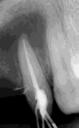

Estudios radiográficos de inicio

En la radiografía lateral de cráneo tenemos (Figura 7) la clase III esquelética con un ANB de -1, hiperdivergencia, aumento de la altura facial inferior, proclinación de los incisivos superiores con 1 a plano palatino de 133°, línea roja sobre la longitud del incisivo superior.

Figura 7. Radiografía lateral de cráneo. Figura 8. Radiografía panorámica.

Estudios radiográficos finales

La radiografía lateral de cráneo en la Figura 11, se observa un ANB de 2° líneas rojas debido al avance del maxilar, una retroclinación del incisivo inferior a 76° líneas amarillas y mejoría de 1-maxilar a 122° líneas azules.

En la radiografía panorámica se ven 24 órganos dentales (Figura 12) después de realizada la cirugía osteotomía Lefort I maxilar de avance y una mentoplastía; las cuatro placas de fijación con sus respectivos microtornillos en el maxilar líneas de color rojo, la fijación con alambre quirúrgico de acero inoxidable señalados azules.